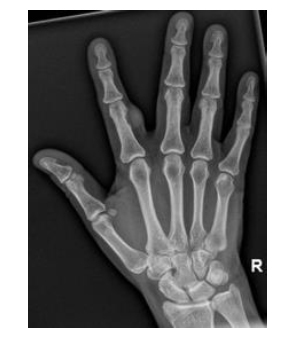

The correct response is Option C.

This is a mucous cyst based on history and examination. Mucous cysts are cysts that arise from the distal interphalangeal joints. They are frequently associated with dorsal osteophytes secondary to osteoarthritis and x-ray studies are useful to establish the severity of osteophytes. X-ray views usually demonstrate osteophytes in proximity to the cyst. The cyst can decompress and clear viscous fluid can be seen. Pressure on the germinal matrix from an enlarging mucous cyst can cause nail grooving, which this patient demonstrates.

These masses are benign and do not require treatment. Aspiration and corticosteroid injection can be considered for nonsurgical treatment. The osteophyte is thought to be an inciting cause of the mucous cyst in these patients and should be removed when surgically treating these patients hence the utility of x-rays in evaluation of the patient. The cyst and stalk are traditionally removed as well.

MRI is unnecessary as clinical examination should be sufficient to establish the diagnosis.

X-ray studies of this patient’s left hand (anteroposterior and lateral) are shown.